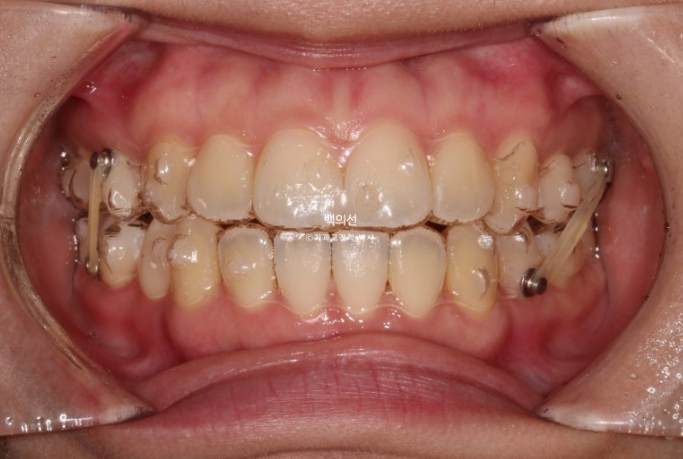

23.05

고무줄을 걸며 인비절라인 치료를 진행합니다.

치료시작 6개월차, 벌써 발치공간이 절반정도 닫힌 것 처럼 보입니다. 이 당시에도 발치한 쪽 어태치먼트가 일부 맞지 않아 어금니가 약간 쓰러지려는 경향이 보였으나 바로 재제작에 들어가진 않습니다.